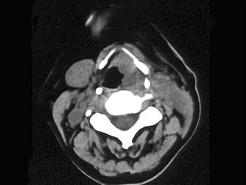

问题 女,54岁,鼻咽部异物感约3个月,PE:左侧声带固定,可见肿物,CT如图所示,应诊断为 ( )

选项 A、慢性增生性喉炎 B、增生型喉结核 C、喉癌 D、喉部血管瘤 E、喉部乳头状瘤

答案 C